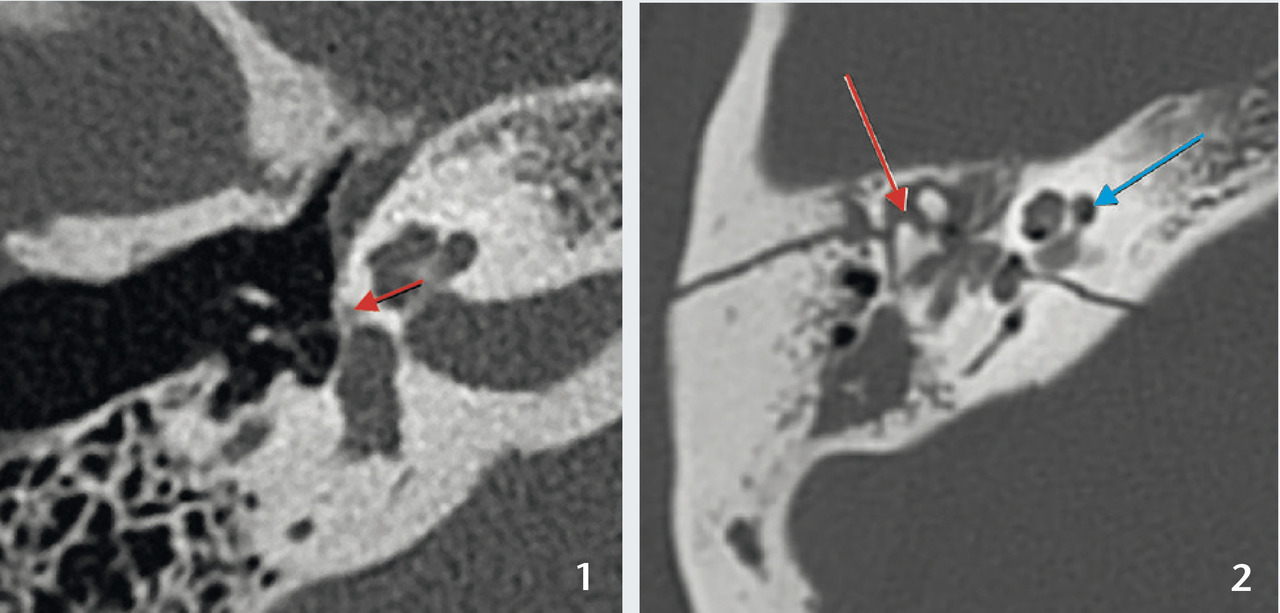

Otospongiose, maladie génétique à transmission autosomique dominante responsable d’une ostéodystrophie de la capsule labyrinthique et notamment d’une ankylose de l’étrier (fig. 1).

– faire le diagnostic positif en montrant le foyer otospongieux : hypodensité préstapédienne infra- ou supramillimétrique qui peut s’étendre autour du labyrinthe antérieur ou postérieur ;

– éliminer un diagnostic différentiel, notamment une déhiscence du canal semi-circulaire supérieur (syndrome de Minor) ;

– détecter des variantes anatomiques qui compliqueraient le geste opératoire : procidence du nerf facial, étroitesse de la fenêtre ronde, fixation de la tête du marteau…